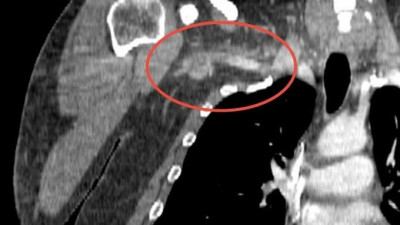

34-летний мужчина обратился за медицинской помощью в больницу в Долгопрудном. Он жаловался на полное онемение правой руки, слабость, головокружение, боль в плече и шее, а также «вспышки» в глазах. В ходе обследования у него был выявлен тромб размером 25 сантиметров.